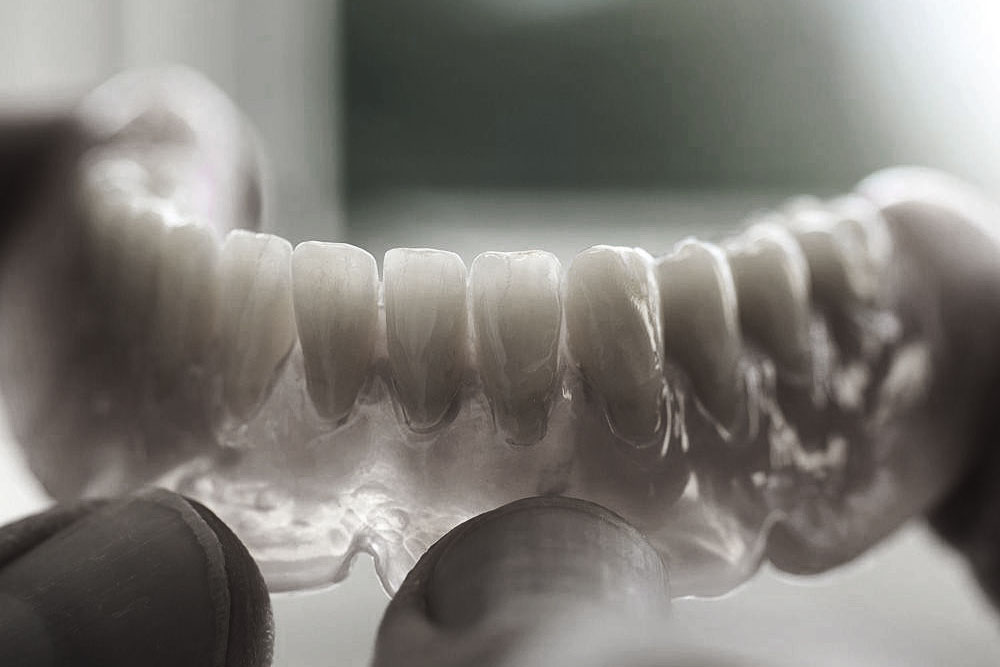

Do uzupełnień protetycznych ruchomych zalicza się protezy, które pacjent w dowolnym momencie może wyjmować z ust. Są to całkowite lub częściowe ruchome protezy akrylowe, nylonowe lub acetalowe oraz wykonane na bazie konstrukcji metalowej protezy szkieletowe. Wymienić tu należy również ruchome protezy typu overdenture wsparte na implantach.

Uzupełnienia stałe w sposób permanentny, lecz nie rozłączny montowane są na zębach lub implantach w jamie ustnej pacjenta. Do stałych uzupełnień zaliczamy wkłady koronowo-korzeniowe, wkłady koronowe, licówki, korony i mosty oraz uzupełnienia stałe oparte na wszczepach śródkostnych.

Korony i mosty wykonane są na podbudowie metalowej, z tlenku cyrkonu lub ceramiki.

Leczenie protetyczne przy użyciu protez stałych przynosi nieporównywalnie lepsze efekty dla pacjentów niż przy użyciu protez ruchomych ze względu na ich stabilne umocowanie w jamie ustnej.